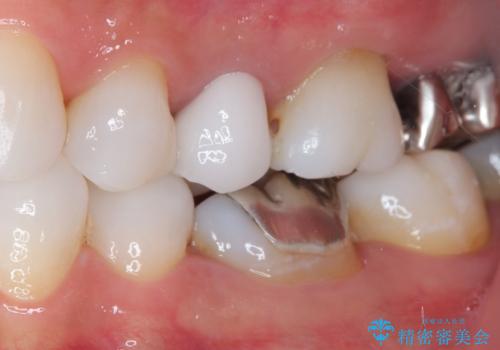

- 奥歯の銀歯とクラウンの縁から見えている歯根を気にして来院された患者様です。

歯根の見えている歯はセラミッククラウンに、詰め物の銀歯が入っている歯はセラミックインレーにて治療を行うこととしました。

笑ったときなど、口を開いたときに目立っていた銀歯や茶色い歯根が気にならなくなり、患者様には大変満足していただけました。